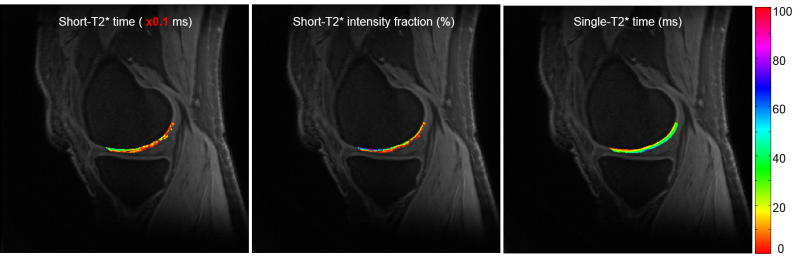

pM2 is a MATLAB-based standalone deployment which can run in a personal computer without MATLAB installed in it. pM2 performs curve fitting to a model of two exponential decays and one constant term: s(t) = A21*exp(-t/T21) + A22*exp(-t/T22) + C + n(t), on a pixel-by-pixel basis in a region of interest (ROI). pM2 uses an iterative NNLS (non-negative least squares) algorithm to search the best fitting at each pixel. It produces seven maps: a21, T21, a22, T22, T2mono, and two R-square (R2). pM2 also calculates the mean and standard deviation (SD) of these fitted parameters

in a user-defined ROI. To define ROI, a separate software will be provided to you for free. An example of pM2 mapping is shown in Figure 2 below. The software package includes a user manual which details how to install and run pM2 on your computer.

Uploading your DICOM images is required. Curve fitting to a two-component model: s(t) = A21*exp(-t/T21) + A22*exp(-t/T22) + C + n(t), on a pixel-by-pixel basis in a region of interest (ROI). Use an iterative NNLS (non-negative least squares) algorithm for the fitting at each pixel. Produce seven maps: a21, T21, a22, T22, T2mono, and two R-square (R2). Calculate their means and standard deviations (SD) in a user-defined ROI. To define ROI, a separate software will be provided to you for free. An example of pM2 mapping is shown in Figure 2 below.

a

b

Figure 2. pM2 bi-component T2* mapping. (a) ROI, long-component T2* time and intensity fraction, (b) short-component T2* time, intensity fraction, and single-component-fitted T2* time.